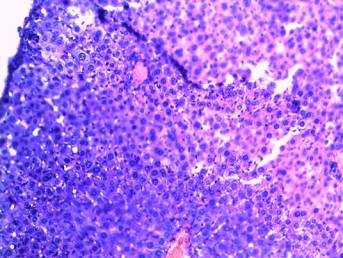

Histological research of experimental

animals internal organs in comparison with control animals internal organs were

also held. Animals’ hearts, livers,

kidneys and stomachs were fixed in Carnoy’s fluid, neutral formalin and flooded

by paraffin for these purposes. Sections were coloured by hematoxylin and eosin

by Van Gieson. In the course of researches was established:

-

endothelial cells of aortha inner membrane have clear nuclea; there are

no destruction of tunica media elastic fibers; myofibrills’ transverse

striation is clear in all heart sections, cardiomyocites’ nuclea contain

sufficient quantity of chromatin, nuclear membrane is thin. There are no

centers of cytoplasm tinctorial properties violation and cardiofibrosis; slight

swelling of heart’s stroma was fixed, which was associated with anesthesia

(picture 1);

Picture 1

Histological

research results

(heart’s stroma slight swelling)